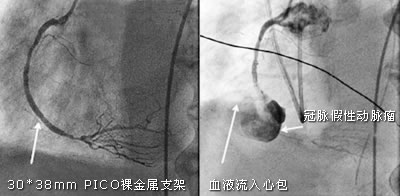

处理:术者顺利开通右冠脉,置入38 mm裸金属支架,狭窄消失,血流TIMI Ⅲ级(图2)。

3个月后患者出现明显胸闷气短,心电图较前无明显变化,超声心动图提示大量心包积液合并心尖下壁运动障碍,可见直径为50 mm的高密度圆形实质(并经CT证实)。急诊冠脉造影示左冠脉支架内无狭窄,血流良好。当显示右冠脉造影时,全场观众一阵嘘声,原38 mm支架中段断裂致假性动脉瘤形成,动脉瘤破裂后血液流入心包(图3)。

图2 开通右冠脉,置入支架 图3 冠脉假性动脉瘤破裂, 百拇医药